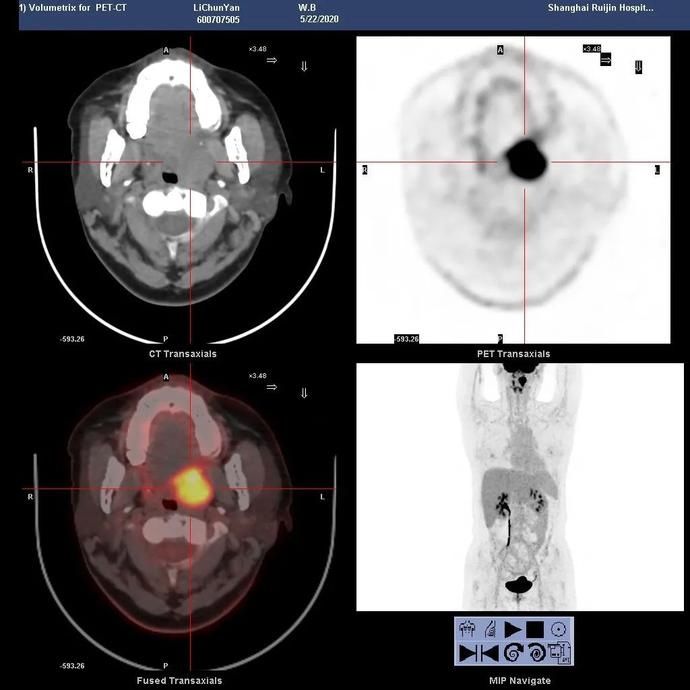

PET-CT

43岁的孙女士,3个月发现自己左侧颈部长了一个肿块,虽然摸上去不疼,但肿块越来越大增大,而且质地挺硬。心怀担心和焦虑的孙女士便来瑞金医院就医,耳鼻喉科向明亮主任通过体检发现,她左侧扁桃体I度肿大,且扁桃体周围黏膜欠光滑,触诊发现左侧扁桃体质地较硬。为了进一步明确诊断,项主任对肿块进行细针穿刺,结果提示低分化转移癌可能。随即项主任为患者办理入院手续,入院后的左扁桃体活检病理冰冻报告结论为低分化鳞癌。

孙女士在得知自己罹患扁桃体癌后愈发焦虑,因为她从其他途径打听到扁桃体癌的手术创伤大,切除范围广,且会影响术后生活质量,不禁夜夜失眠,人消瘦了不少。向主任得知了孙女士的困扰,向她详细介绍了目前瑞金医院采用的新技术--口咽恶性肿瘤的微创治疗术,打消了孙女士的顾虑。